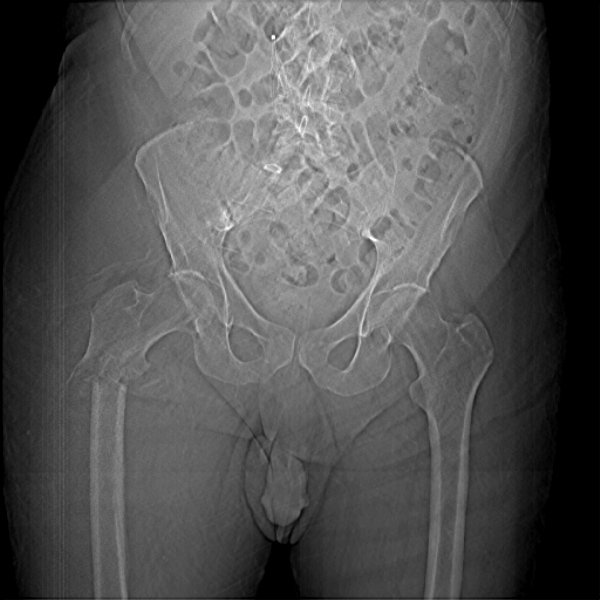

Return to Pathologic Fracture (Femur)